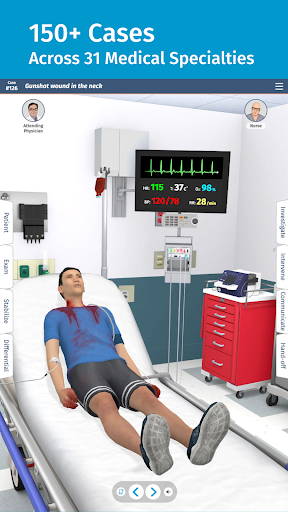

• 200+ thư viện trường hợp được biên soạn và đánh giá bởi các bác sĩ lâm sàng chuyên gia

• Hơn 30 chuyên khoa chẩn đoán, bao gồm Y học cấp cứu, Sản phụ khoa và Nhi khoa

• Hơn 20 hình đại diện thực tế, bao gồm bệnh nhi và người lớn

Mỗi trường hợp đều là một thách thức mới trong Full Code: từ chẩn đoán thông thường đến các bệnh hiếm gặp. Bạn không chỉ giới hạn ở bệnh viện—Full Code đã mở rộng sang nội dung trước khi nhập viện và EMS. Ra khỏi khoa cấp cứu và vào xe cứu thương để ứng phó với mọi tình huống mới!